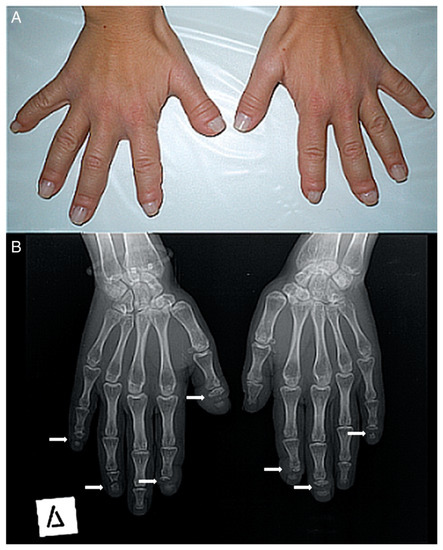

La vía de señalización NOTCH se activa cuando el ligando de una célula se adhiere al receptor de la célula, provocando la separación del dominio intracelular, que viaja al núcleo de la célula donde comienza a completar su función.Figure 2. (A) Photograph of a patient’s hands. Many of her fingers are thick (predominately the right thumb) with pseudo-clubbing. (B) Anteroposterior radiograph of a patient’s hands. Osteolysis of the distal phalanges is found in most of the fingers (only the left thumb, the left fourth, and the right third fingers have a normal appearance). In all lesions, osteolysis has a transverse pattern across the width of the terminal phalanx (white arrows).

Figura 2. ( A ) Fotografía de las manos de un paciente. Muchos de sus dedos son gruesos (predominantemente el pulgar derecho) con pseudo-discotecas. ( B ) Radiografía anteroposterior de las manos de un paciente. La osteólisis de las falanges distales se encuentra en la mayoría de los dedos (solo el pulgar izquierdo, el cuarto izquierdo y el tercer dedo derecho tienen un aspecto normal). En todas las lesiones, la osteólisis tiene un patrón transversal a lo ancho de la falange terminal (flechas blancas).-middle adulthood (ages 36–65)